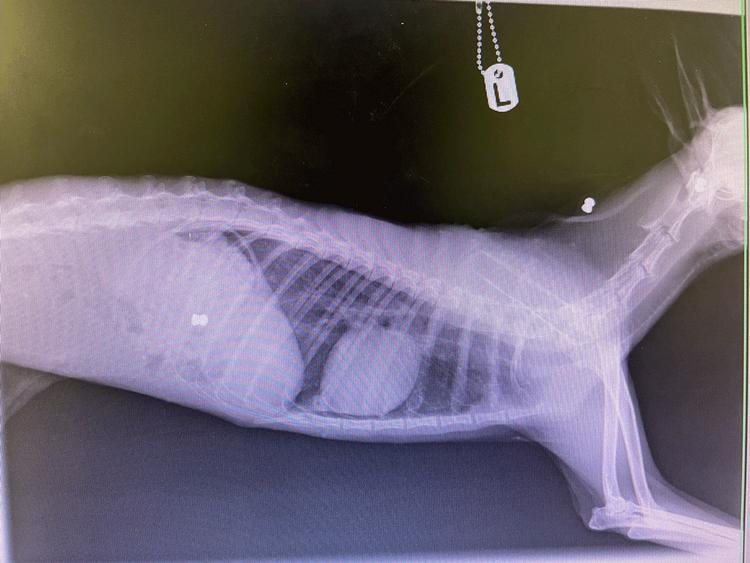

Weliketogiveourpatientsallthesupporttheyneedtogetthembacktothewild,evenifthat meansasilverspoonservice.Thisyoungfemalearrivedwithasmallwoundtoherback. Thankfully,theflyeggsonherhadn'tyethatched,but,worryingly,herbreathingappearedtobe causingheralotofdiscomfort

WithanX-rayconfirmingpneumonia,the littlehoglethasbeenreceivingsome extraTLCfromourvetteam,withsupport feedsandregularnebulisationtoease herbreathing.

Happily,sheisnowsportingavery healthyappetite,andwearehopefulthis littlehogisonherwaytohersecond chance